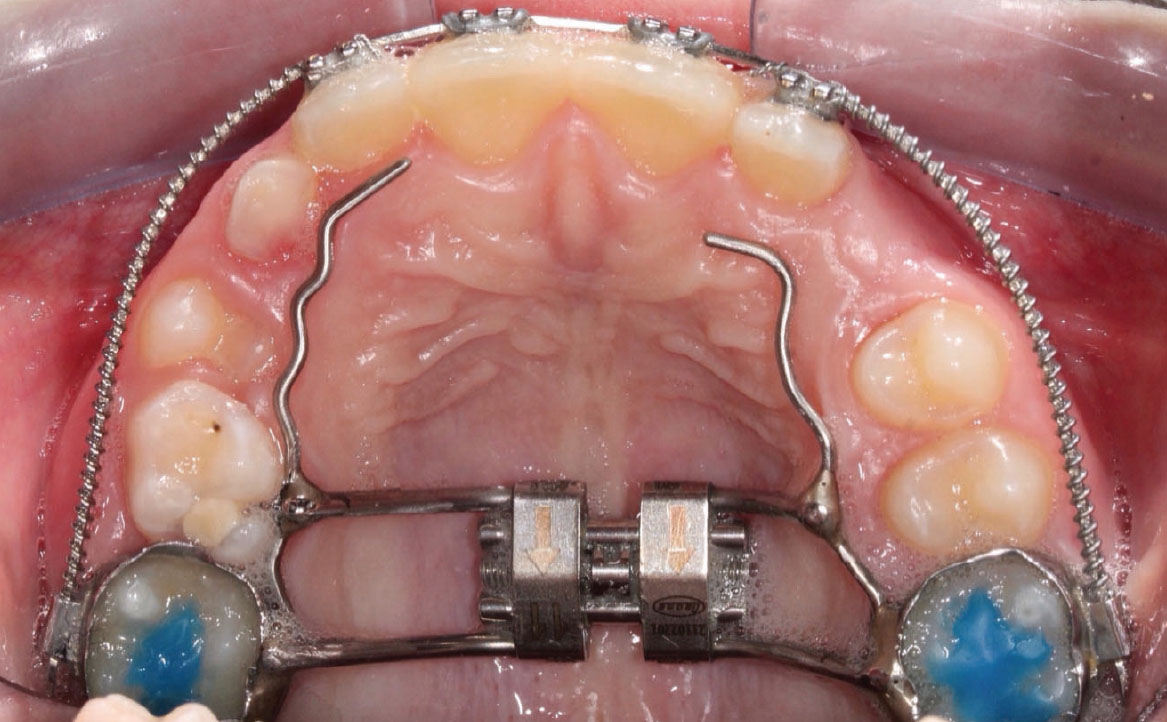

Fig. 6A Foto dell'arcata superiore.

A seguito di scansioni intraorali, viene realizzato un disgiuntore palatale rapido, cementato con cemento vetroionomerico tramite bande su 16 e 26.

Vengono eseguiti dei rialzi occlusali sui primi molari permanenti superiori per consentire la disclusione.

È stata prescritta un’attivazione al giorno del REP monitorando settimanalmente il paziente fino all’ottenimento di un’ipercorrezione trasversale.